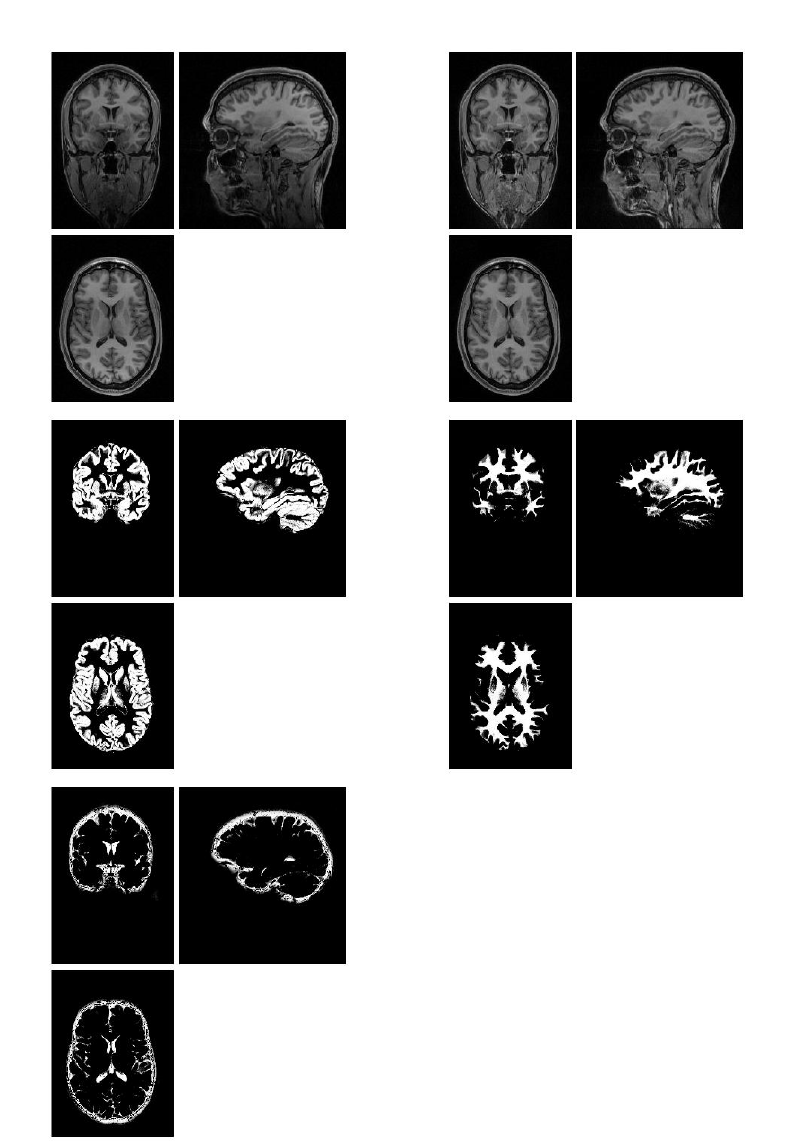

29 Old Segment 211

29.1 Data ............................................212

29.2 Output Files .......................................212

29.2.1 Grey Matter ...................................215

29.2.2 White Matter ...................................215

29.2.3 Cerebro-Spinal Fluid ...............................215

29.2.4 Bias Corrected ..................................215

29.2.5 Clean up any partitions .............................215